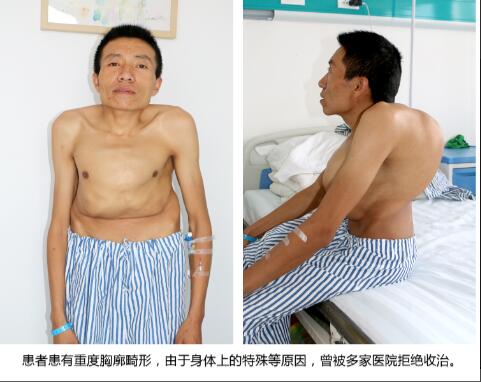

主诊医生丁德刚主任,在先进眼看到胡这志时,就明显感到这位患者的特殊——这位年近40岁的中年男子,由于身体重度畸形,身高只有130厘米左右,前胸整体严重突出,基本与面部垂直持平;背部左侧畸形,骨骼高出背部平面近30厘米。

可这些也仅是体表上的显现,当丁主任拿到检查结果时是不免心头一紧——肌酐、尿素、尿酸等指标均超出正常指标数倍,已经开始呈现出尿毒症的检验结果及体征。患者的左肺已经从身体的右侧胸腔挤压到左侧胸腔,左侧肺功能已经有效消失,同时右侧肺功能也受到了影响,肺活量不到正常人的一半,呼吸很浅很快,并伴有呼吸性酸中毒,并且心脏功能很不好,平时还需要用药物来保持心率;但加严重的是患有结石的输尿管严重畸形,他的输尿管严重扭曲,左侧输尿管已蜿蜒扭转到身体右侧,从右侧延至膀胱。检查结果显示患者结石的位置还偏偏位于左侧输尿管上段,这也就意味着如果进行手术,则需要将输尿管镜一直蜿蜒延伸到输尿管的尽头才能进行,这些都使手术难度大幅度增加,在从医三十多年,临床经验非常丰富的丁主任看来,这个病例也是非常棘手的。